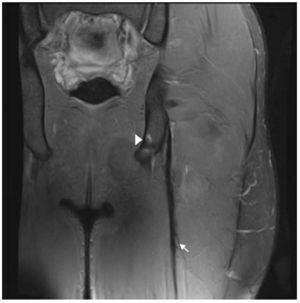

Nineteen years old professional football player suffered sudden pain in his posterior, upper part, thigh when sprinting and was unable to play. Clinical signs showed an acute ham-string strain (painful palpation, limited range of motion (ROM), decrease of strength, painful stretching and difficulty to walk normally). MRI was performed 24 h post-trauma with a 3-T scanner (Titan Vantage, Toshiba). LHBF injury and its characteristics are described in Figs. 1 and 2. The final diagnosis was a proximal MTJ injury of LHBF localized at 10 cm from the ischial tuberosity and 6 cm from the onset of the MTJ. The expected lay-off time was 7-8 weeks. The recovery treatment consisted basically in 3 stages: physiotherapy measures, strength and neuromuscular training in the gym and specific individual football training in the field.

Figure 1 Coronal and axial T2 Fat-saturated images of the left hamstring showing focal partial tear (fiber disruption) in the proximal MTJ of LHBF represented by an area of high signal intensity adjacent to the MTJ (arrow). Note also few disrupted muscle fibers in semitendinous (+). Semitendinosus muscle belly (ST), proximal long head of biceps femoris (LHBF), semimembranosus tendon (arrowhead) and sciatic nerve (*). Feathery pattern of muscle edema can be seen in coronal view.